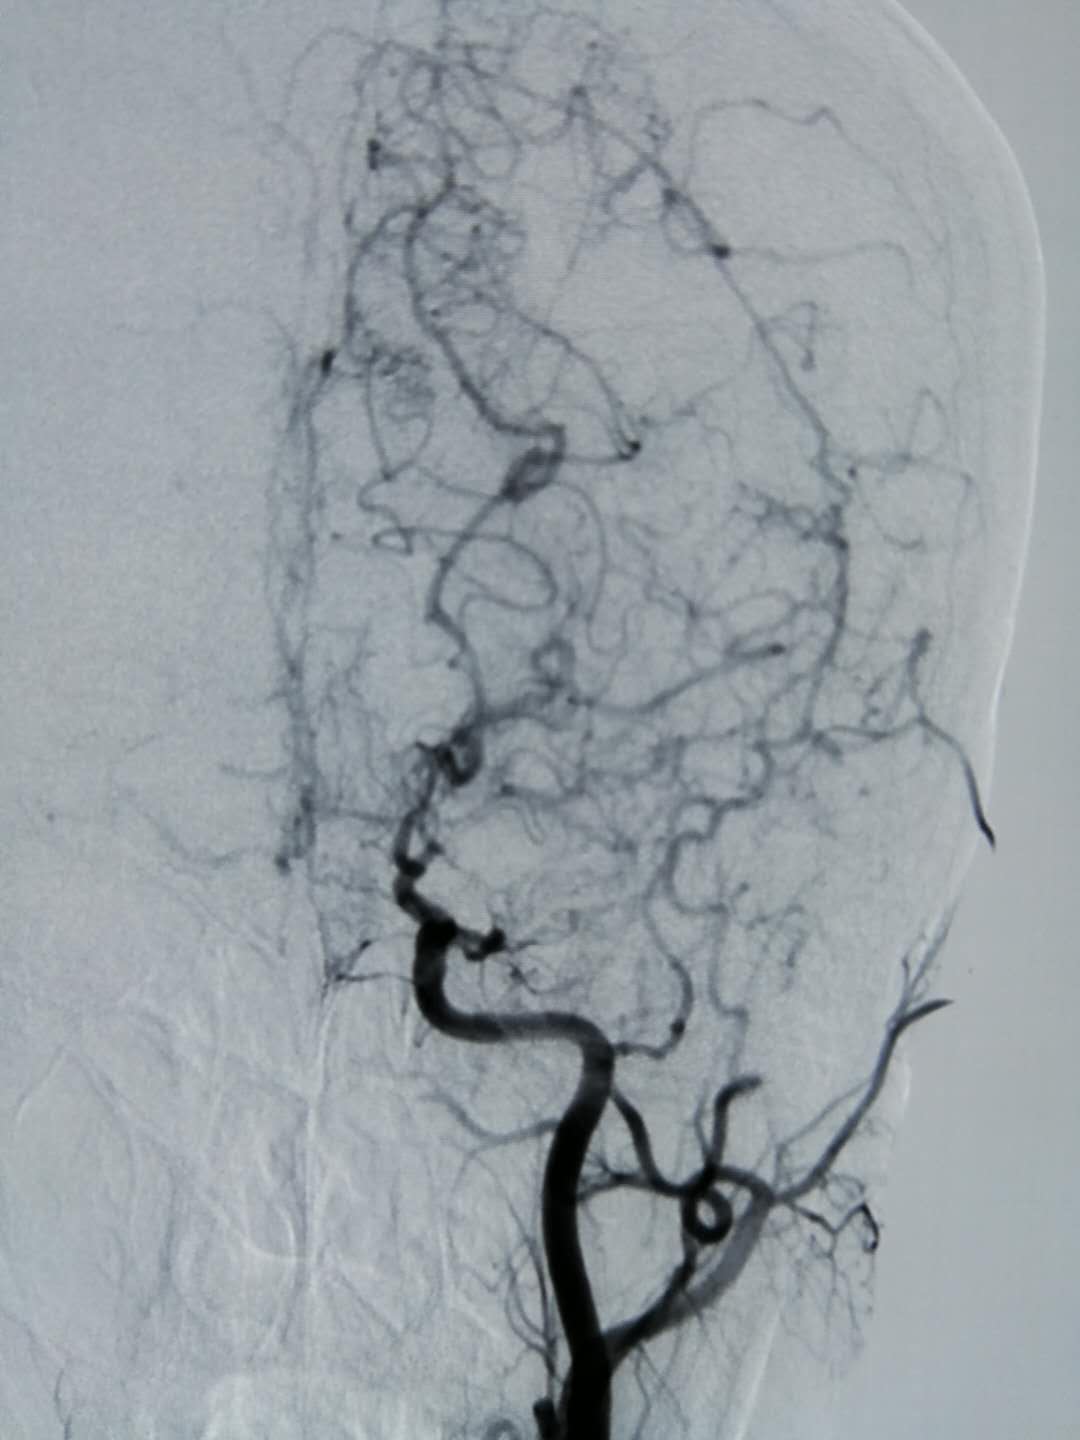

20200407sxw—烟雾病造影

图片尺寸2000x2667